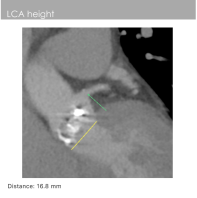

左冠开口高度:16.8mm

右冠开口高度:15.7mm

2)虽然患者比较适合TAVR,但是也有一定的手术风险。患者的左右冠脉开口均不高,瓣叶均可到达左右冠脉开口层面,窦内空间不大,存在冠脉闭塞风险,因此需要在球囊预扩时,对冠脉风险进行评估,确定无风险后再经行瓣膜植入。